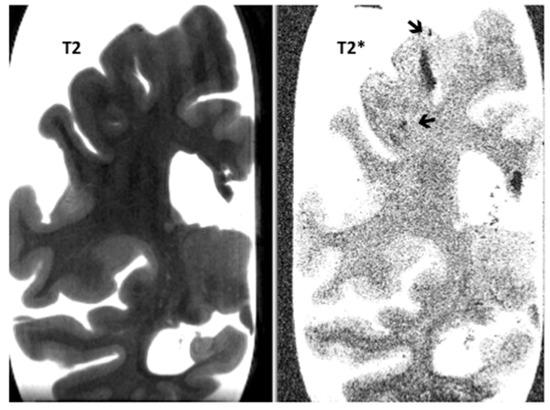

Post-Mortem 7.0-Tesla Magnetic Resonance Imaging of the Hippocampus in Progressive Supranuclear Palsy with and without Cerebral Amyloid Angiopathy

3. Results

| Hippocampal micro-infarcts | 0.0 (0.0) | 0.2 (0.4) | NS |

| Hippocampal micro-bleeds | 0.9 (0.6) | 0.4 (0.5) | NS |